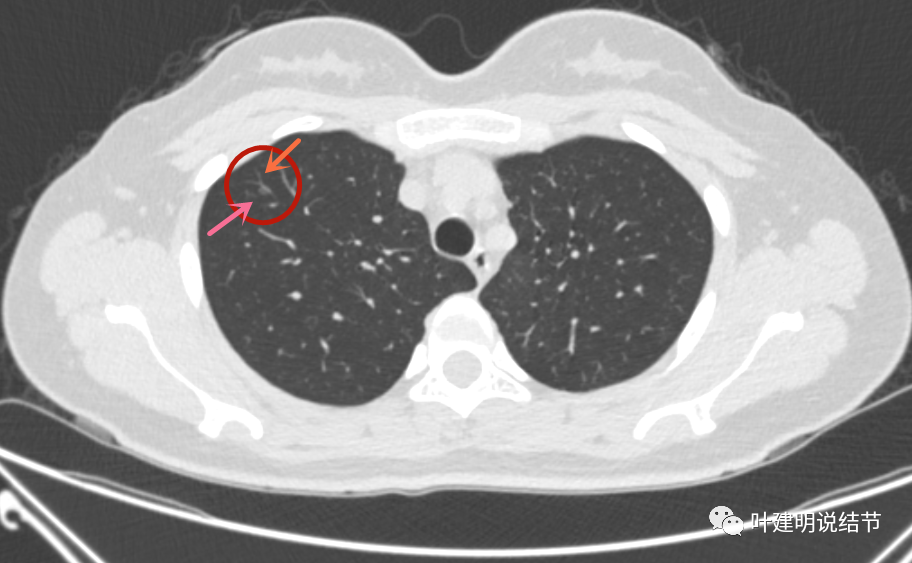

查体发现右肺磨玻璃结节,三个月后病灶消失

混合磨玻璃结节,伴有胸膜牵拉——肺腺癌